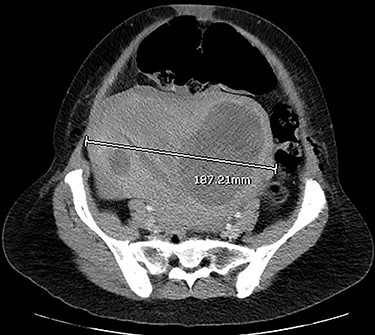

CT images suggested complete obstruction of the sigmoid colon secondary to impingement by polymyomatous uterus (see Fig. 2). The transition point was directly posterior to a large fibroid which appeared necrotic, shown in Fig. 3. Although the pathology was arguably mechanical, it was decided to trial conservative management, consisting of NGT insertion, enemas, laxatives, electrolyte optimization, cessation of constipating medication and frequent mobilization. Within 24 h, the patient began to pass flatus. Her symptoms resolved completely after 72 h and she was discharged with gynaecology follow-up.

CT abdomen and pelvis with venous phase contrast, axial view. Polymyomatous uterus at its maximal width of 187.21 mm, 2 days postpartum. Note the larger fibroid on the right, reported to show necrotic changes. Dilated bowel loops visible anterior to the uterus.